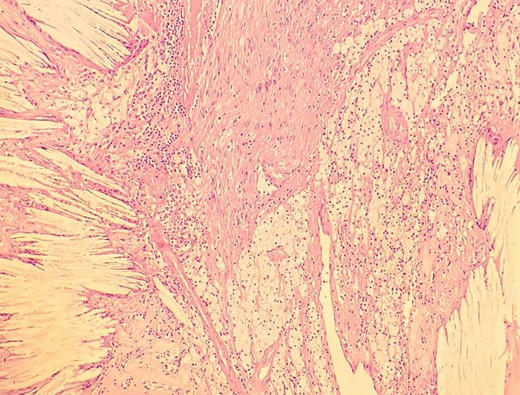

A man in his 30s presented with symptoms suggestive of irritable bowel symptoms with increased bowel movements coinciding with the onset of colicky abdominal pain for the past 8 months. The bowel movements relived his pain and had no remission from his symptoms. He had no relevant medical comorbidities in the past. The patient had normal vitals. There were no physical exam abnormalities except for a slight fullness in the left renal angle (Fig. 1). There was nothing significant on a rectal examination. An X-ray of the chest showed normal findings. Blood investigations showed: haemoglobin 130 g/l, total leukocyte: 7.4 × 109/l, serum creatinine 0.52 mg/dl, fasting blood sugar 90 g/dl, alanine transaminase 26 U/L, aspartate transaminase 42 U/L, alkaline phosphatase 32 U/L and total bilirubin 0.8 mg/dL. Ultrasonography showed a 10-cm mass, with mixed echogenicity. Posterior to the left kidney. Colonoscopy was normal. An abdominal CT scan showed a paravertebral tumour with peripheral enhancement and heterogenous contrast within the tumour (Fig. 2). The tumour showed high intensity on a T2-weighted MRI (Fig. 3). The left kidney and colon were displaced anteriorly. Fine-needle aspiration biopsy was inconclusive. The clinical diagnosis was a retroperitoneal schwannoma. On laparotomy, the left colic vessels appeared to be splayed by the tumour (Fig. 4). The tumour 11 × 6 × 3 cm3 (Fig. 5), which seems to be arising from the L2 nerve, was resected completely (Fig. 6). The patient had no sensory or motor loss postoperatively. He was discharged without complications on the 10th postoperative day. His colonic symptoms had disappeared after surgery. The gross appearance of the resected tumour showed cysts and haemorrhage patches (Fig. 7). Histopathology showed areas of hypercellularity (Antony A) and hypocellularity (Antony B) with degenerative changes leading to nuclear atypia and cystic spaces, typical of an ancient schwannoma (Figs 8–11). Immunohistochemistry with S-100 was positive (Fig. 12). He was devoid of digestive symptoms or radiological evidence of recurrence at 12 months.

Low-resolution 200x H&E histopathology image of the tumour showing hypocellular (Antony B) areas.